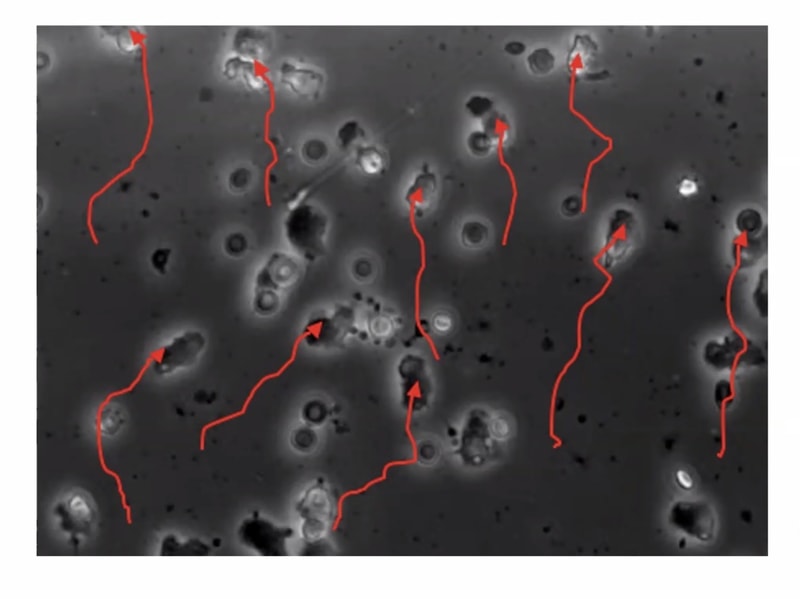

In the young, these cells move fast and directly towards a pathogen (towards the top of the screen in these slides edited from the presentation). In the older subjects, it's not a pretty picture:

The super interesting part of all this is the system of signalling in the cell that achieves this, and what we know about them.